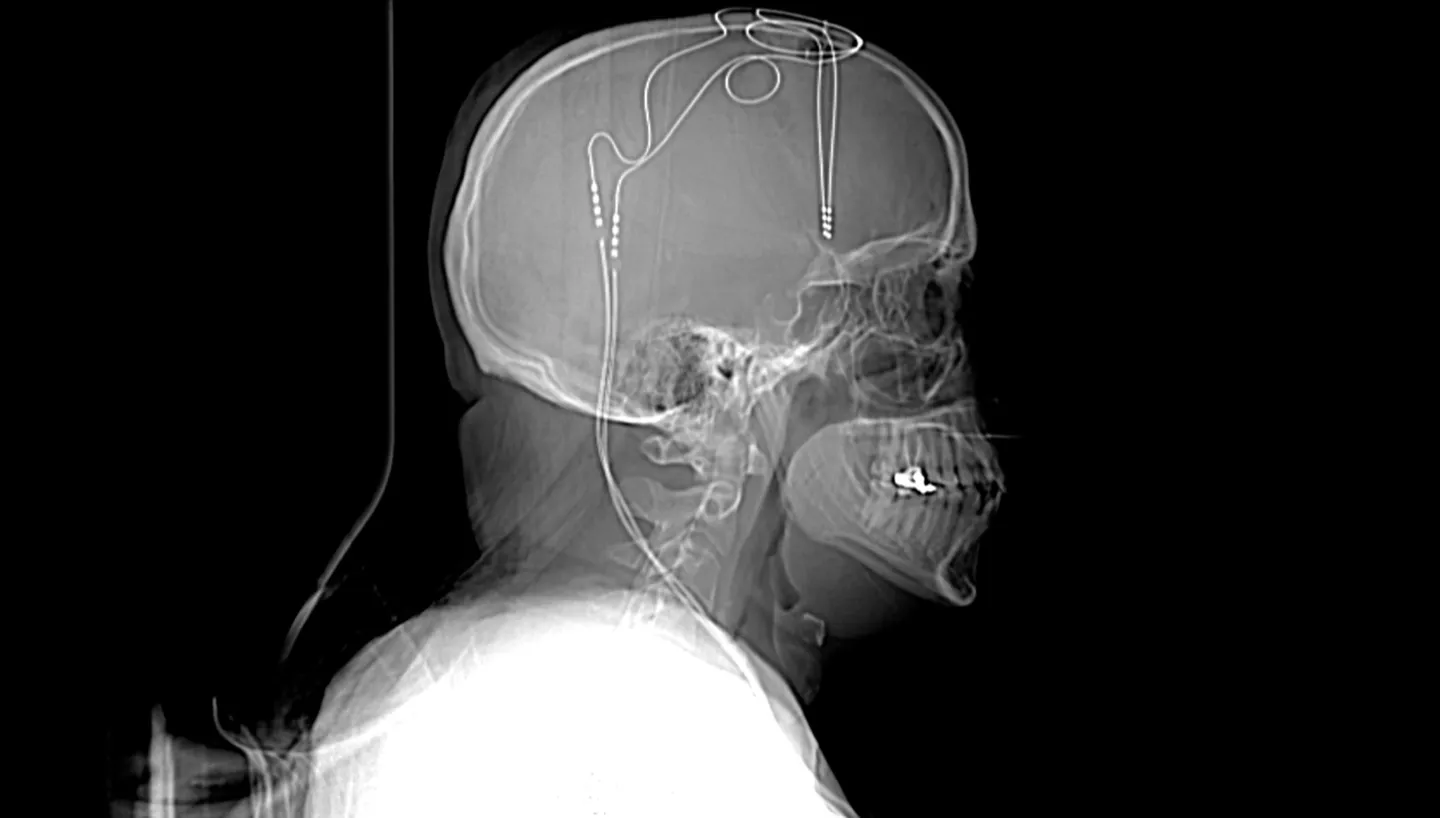

這是喬恩·尼爾森 (Jon Nelson) 的 X 光片,他自願接受實驗性抑鬱症治療。該圖像顯示了植入他大腦中的兩根細電極線。